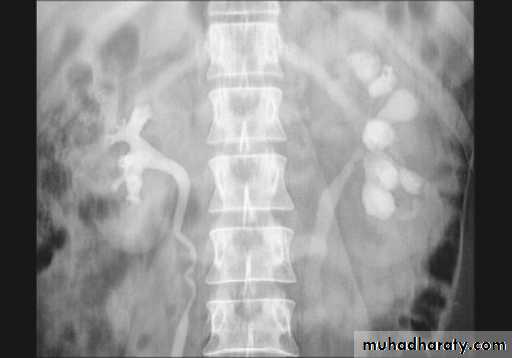

A. First a plain x-ray of the abdomen is taken before the injection of the contrast media, also known as A KUB (kidney, Ureter and Bladder). Calcification & stones may be obscured & missed by contrast media if plain film not takenfirst .B. Films taken after injection of contrast’ medium:

A series of x-ray films are taken after injection of the contrast. Each film is taken at a time interval determined by the radiologist who is supervising the procedure.

1. Nephrogram phase (Immediately after injection of contrast) .

2. Pyelogram Phase (1- 5) minutes after injection of contrast) .3. After 10 minutes with compression, to get better distention of the pelvis and calyces.

4. Full length film after release of compression .